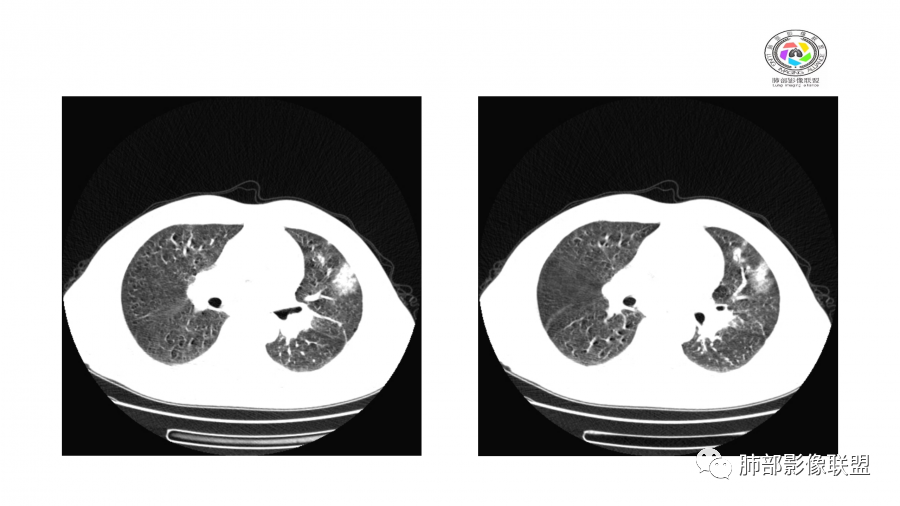

患者,男,49岁,初次以头晕呕吐肾功能异常入院,后期伴双下肢水肿,CT示双肺多发斑片及结节影,部分周围伴晕,部分内部可见支气管穿行,多次复查可见部分病灶略吸收及新发病灶出现,最后一次复查双肺多发磨玻璃样改变,综合考虑血管炎,最后一次伴肺水肿可能

中年男性,高血压,肾功能衰竭,贫血病史,尿潜血阳性。3.8双肺野多发斑片磨玻璃实变影,结节影,边缘模糊,周围有晕征,内见支气管充气征,主要沿支气管血管束分布,部分胸膜下分布,3.12号病灶有吸收好转,4.8号斑片实变影基本吸收,主要沿支气管血管束分布结节影,边缘平直收缩,4.28病灶大部分吸收好转,双肺支气管血管束增粗,有少量结节影。考虑ANCA相关性血管炎可能性大,第一次片子觉得隐球菌不排除,但是后面没有抗真菌治疗就吸收了,觉得隐球菌可能性不大。

胸部CT:双肺多发实性斑片影,散在GGO。实性斑片周围可见晕征、边缘模糊不清,病灶于肺外围区域优势分布。肺门区血管影增粗,支气管套袖,目测肺动脉增粗。3月、4月复查肺内实性斑片病灶呈游走性,此起彼伏。

10天后:病灶继续吸收好转

伴随少量胸水

应该与气道无关

符合间质、血管来源病变

此起彼伏

有肾功能不全

支持与肾病相关

警惕血管炎